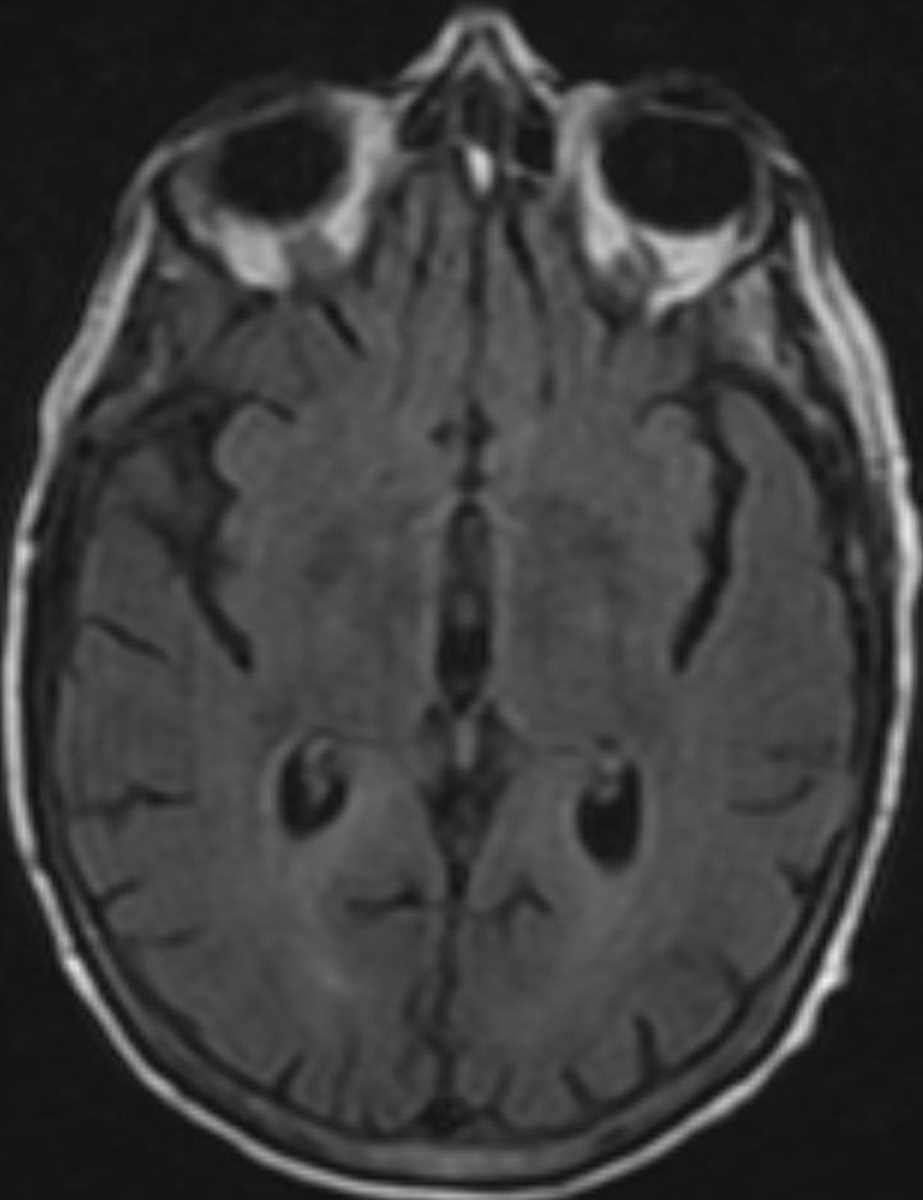

HIV Leukoencephalopathy

This patient had clinically known HIV encephalopathy and typical imaging findings are demonstrated in this case. There is global cerebral volume loss, as well as extensive T2/FLAIR hyperintensity involving the periventricular white matter and centrum semiovale symmetrically, without associated enhancement.